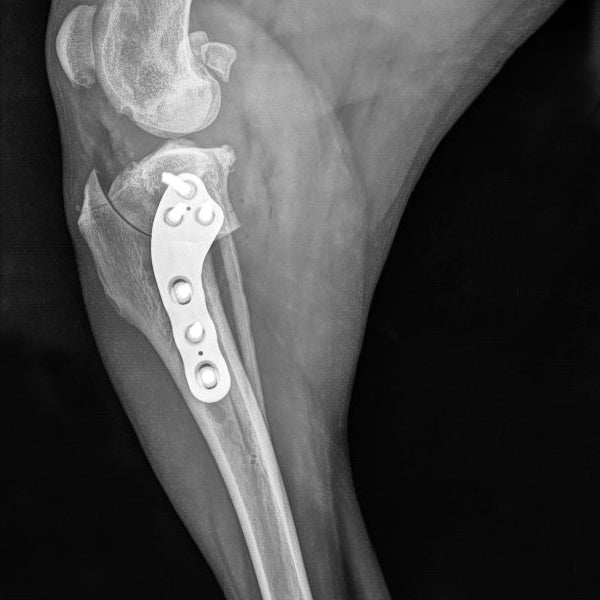

Welcome to our comprehensive Tibial Plateau Leveling Osteotomy (TPLO) course, designed to equip veterinarians with the advanced skills and knowledge to acquire a foundation in this common and crucial orthopedic procedure. TPLO has become the gold standard for treating cranial cruciate ligament (CCL) rupture in dogs, offering superior outcomes, improved long-term joint stability, decreased rates of downstream meniscal tears, and minimal progression of osteoarthritis.

*Orthopedic experience required to attend this course (bone handling, fractures, and/or other CCL techniques)

6. Explore the surgical technique of the TPLO step-by-step, covering key aspects such as osteotomy planning, plate selection, implant placement, and intraoperative decision-making.